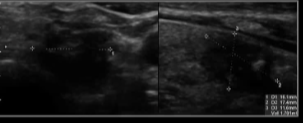

经皮乙醇注射:在超声引导下,将20-22G针头插入囊性结节。几乎完全抽吸囊性内容物,然后注入约为原始体积50-70%的无水酒精。

轻度敷料压迫 敷10分钟后再抽吸。